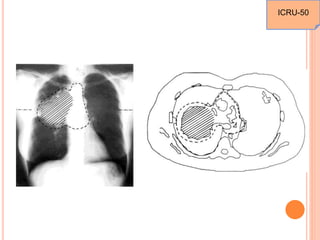

THE EFFECT OF MOTION

ICRU-62

INTERNAL MARGIN

A margin that must be added to the CTV to compensate for

expected physiologic movements and the variations in

size, shape and position of the CTV during therapy in

relation to the Internal Reference Point and its

corresponding Coordinate System. Motion is associated

with adjacent respiratory and digestive organs.